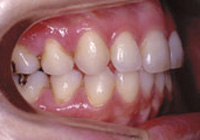

症例4:上顎前突(出っ歯)

治療前

治療後